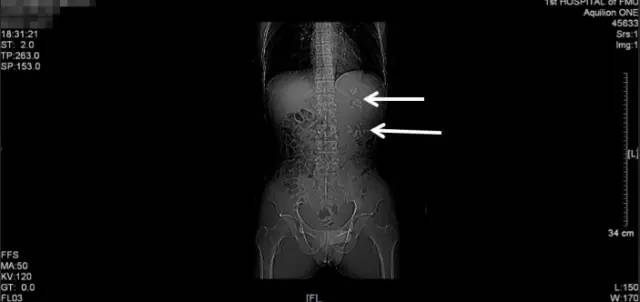

第二次来福建医科大学附属第一医院复查KUB检查结果

通过与4个月前的片子对比,我们可以看到虽然经过了两次手术,但是左肾区仍然遗留了大量而且分散的结石,甚至输尿管上段都有结石卡住(白色箭头所指结石),所以其症状仍然反复。

从他复查的这个KUB上,我们可以看到,左肾仍然有很多结石,而且还有结石掉到左侧输尿管上段引起了梗阻。这种结石如果不取干净,他肾脏里的结石就会时不时掉下来一颗两颗的,堵住输尿管,最终一定会把这个肾脏搞坏掉,我果断通知患者立马住院。